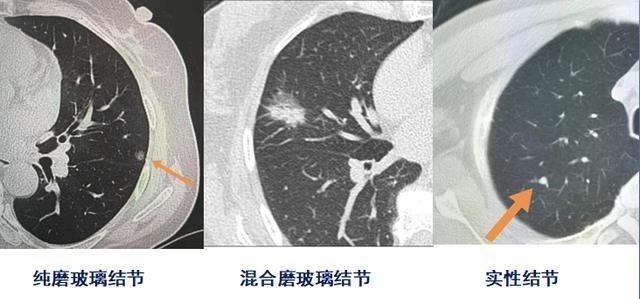

根据这个速度统计,就衍生出两个比较实用的观点:1.实性小结节,如果随访时间大于2年,未见结节生长,基本就要考虑良性结节了;2.磨玻璃结节大多属于惰性病灶,随访时间应大于2年。早期肺腺癌,上面3种形态的结节都可以见到,其中磨玻璃成分越多,通常代表肿瘤细胞分化程度越好;但小细胞肺癌一般表现为实性肺结节,并且大多数生长快,原发灶很小的时候就可以发生转移。问题2,磨玻璃结节既然生长缓慢,为什么医生会建议3个月就复查第一次?会不会辐射超标?对于肺结节生长速度的统计,取得是平均数,有少数磨玻璃样肺结节也会快速增长,需要积极手术处理,不应漏网。一般来说,3个月内有增长的磨玻璃结节,风险往往较大。我们举两个例子:例1,小于1厘米的纯磨玻璃结节,病理是浸润性腺癌